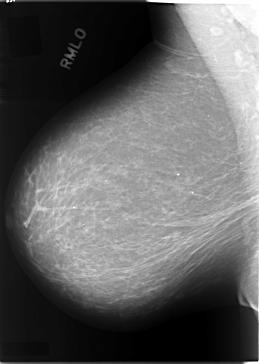

C_0084_1.RIGHT_MLO

LEFT_MLO LINES 5896 PIXELS_PER_LINE 4088 BITS_PER_PIXEL 12 RESOLUTION 50 OVERLAY

FILE: C_0084_1.LEFT_MLO.OVERLAY

TOTAL_ABNORMALITIES 1

ABNORMALITY 1

LESION_TYPE MASS SHAPE LOBULATED MARGINS CIRCUMSCRIBED

ASSESSMENT 4

SUBTLETY 5

PATHOLOGY MALIGNANT

TOTAL_OUTLINES 1

BOUNDARY